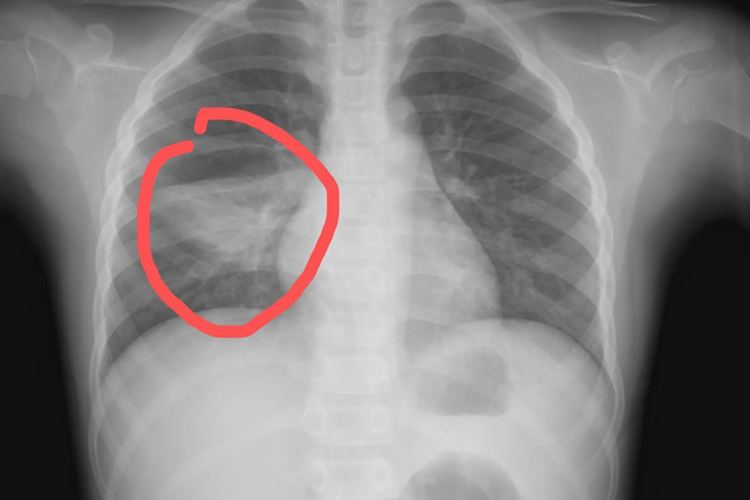

儿童肺炎一般是指小儿肺炎,胸片可显示两肺中、下野有散在的大小不等的斑片状阴影。

小儿肺炎在检查胸片时,可表现为两肺中、下野有散在的大小不等的斑片状阴影,当病灶融合扩大时,则可见大片状阴影。同时,患儿可有发热、咳嗽、气促等临床症状。